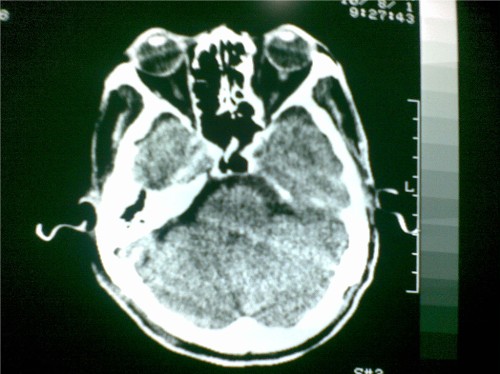

标题: CT28096:男,75岁,外伤10天后,现在恶心、呕吐。是硬膜下积 [打印本页]

标题: CT28096:男,75岁,外伤10天后,现在恶心、呕吐。是硬膜下积

硬膜下积液、右侧基底节、左侧放射冠腔梗。

硬膜下积液、多发性腔梗。

1)双侧额颞顶部硬膜下积液;建议必要时复查。2)多发性腔隙性脑梗塞。